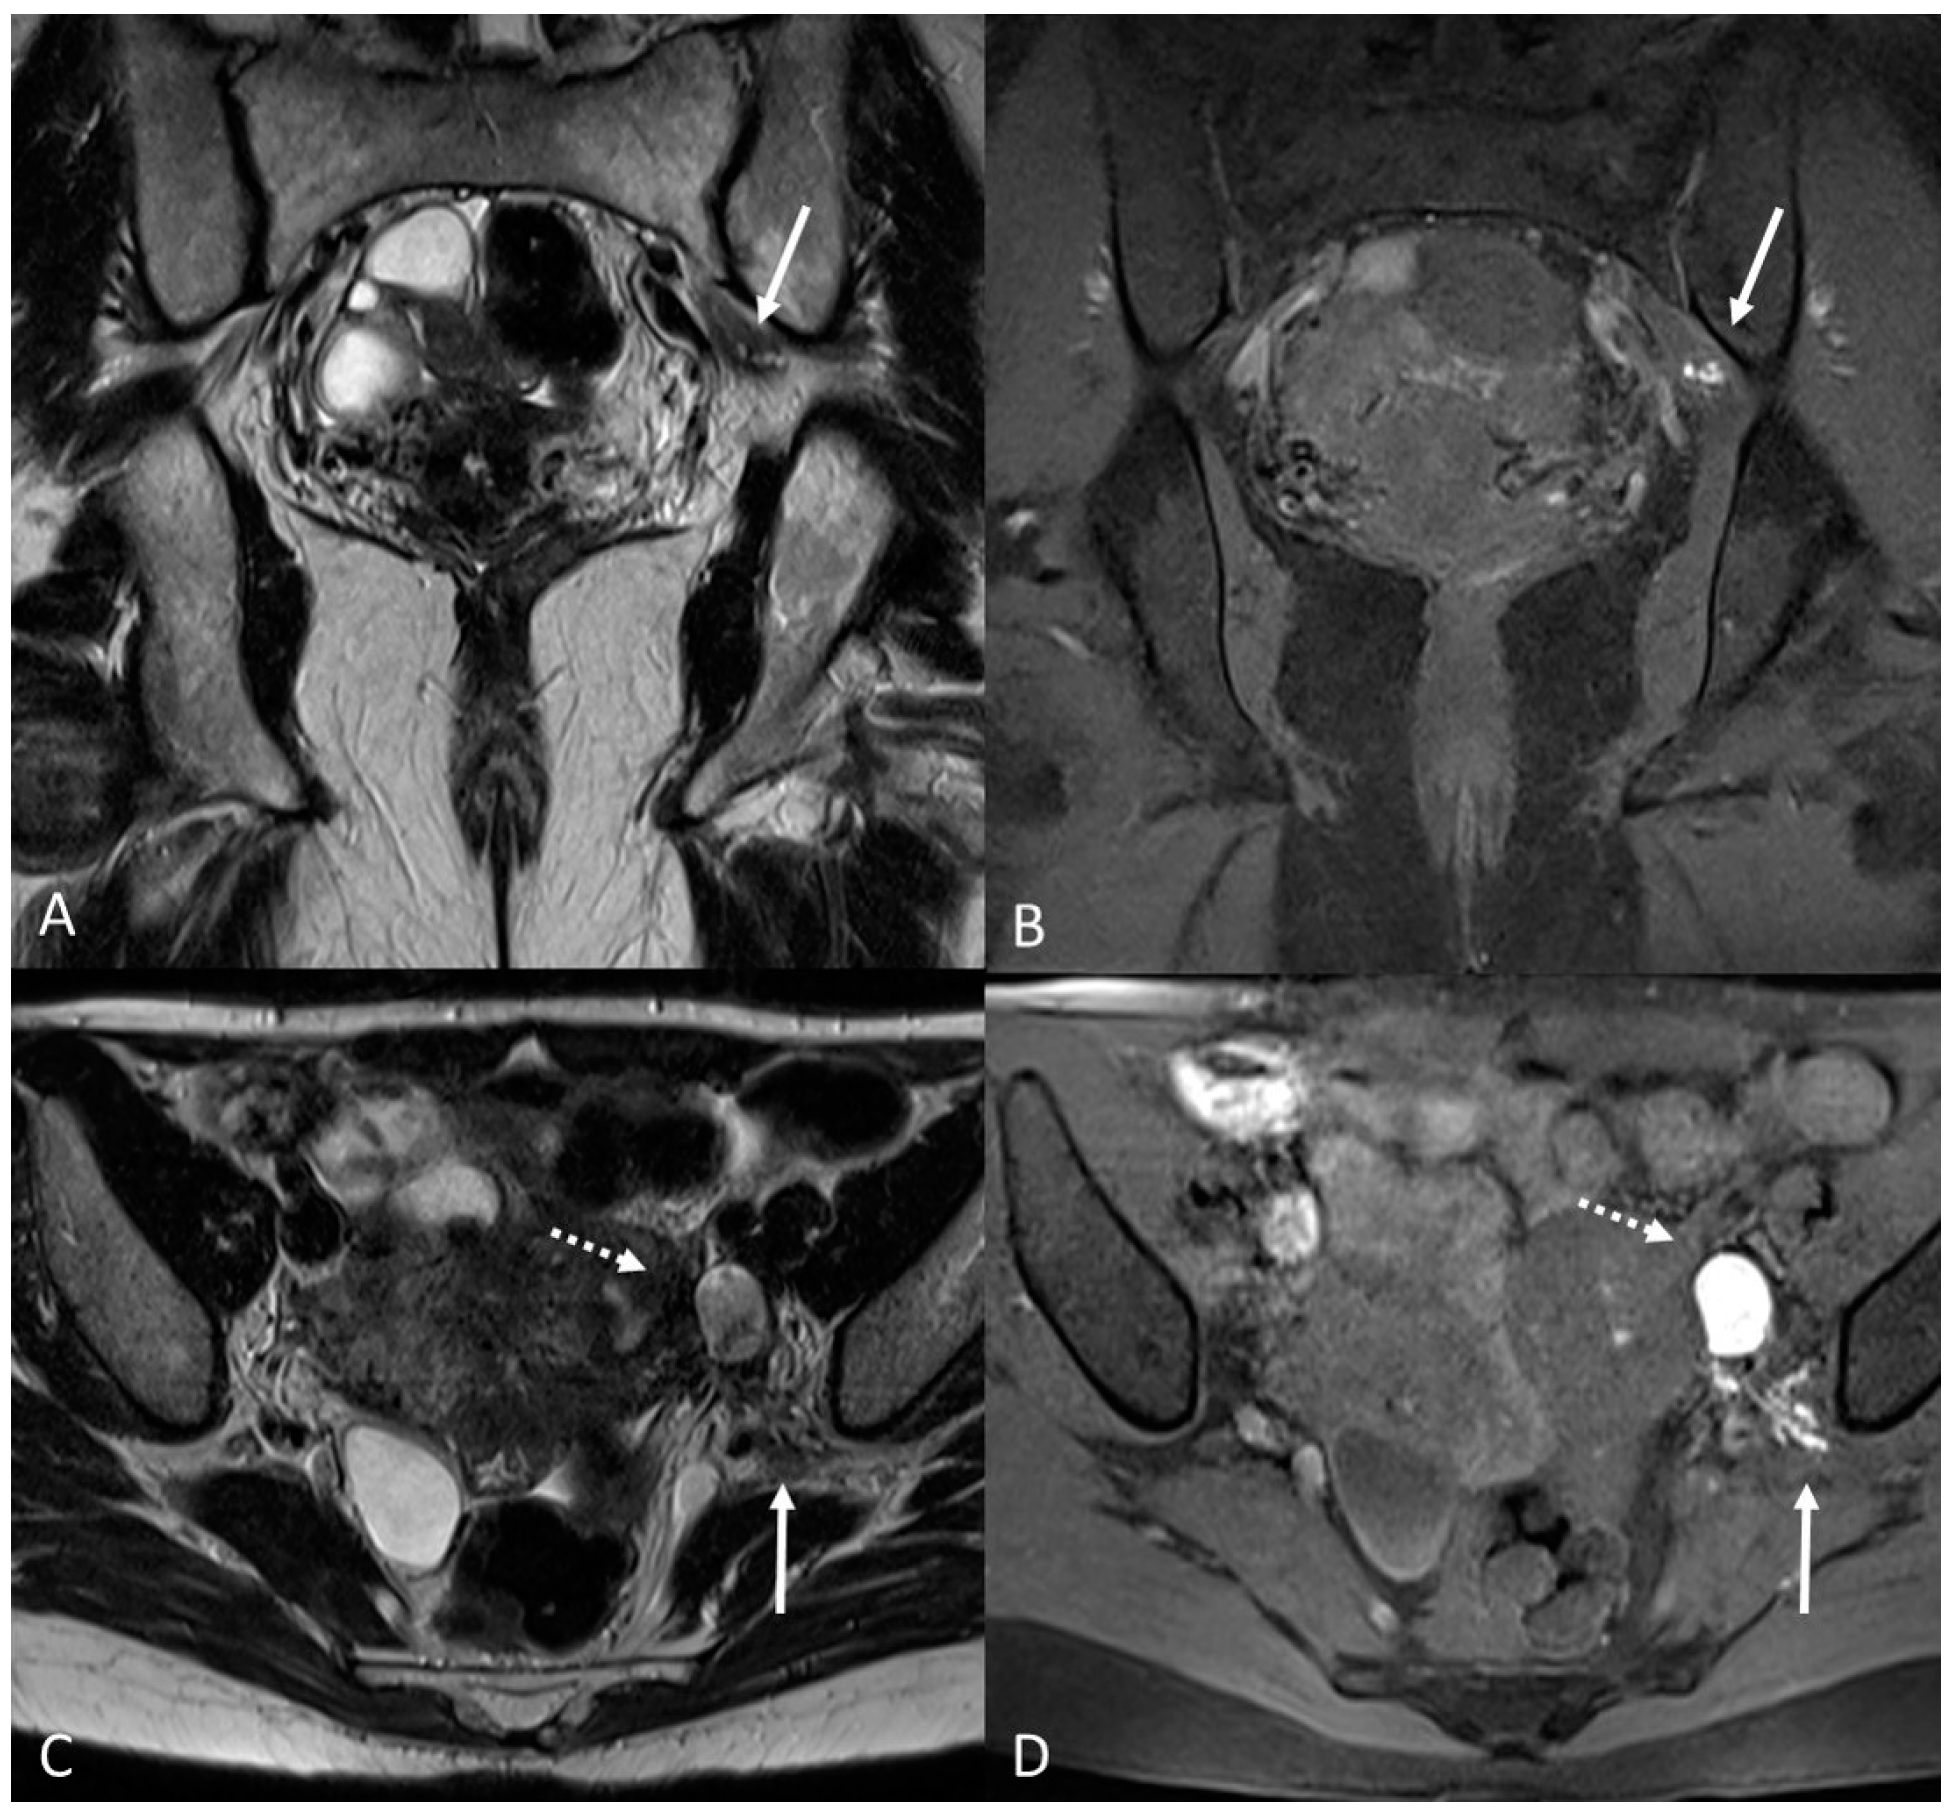

There are also cases of involvement of peripheral nerve plexuses of the pelvic region, such as sciatic, obturator, femoral, and pudendal nerves and their branches (Figure 14).

Figure 14.

Localization of the left sciatic nerve and para-uterine endometriotic nodule in a 43-year-olf female with a previously diagnosed endometriosis and surgery approach, accepted at the emergency department for reported left lumbar pain, which radiates to the left side and is associated with episodes of vomiting. (A) Coronal T2WI. Involvement of peripheral nerve plexuses of the pelvic region (sciatic nerve) appearing as a hypointense plaque (white arrow); (B) Coronal fat-suppressed T1WI. The lesion shows small hematic foci (white arrow); (C) Axial T2WI. Para-uterine endometriotic nodule (white dotted arrow) shows variable intensity ranging from low intensity (referred to as shading) to intermediate or high intensity; (D) Axial T1WI. Para-uterine endometriotic nodule with hyperintense signal (white dotted arrow).

MRI is the best imaging modality to investigate neural involvement [78].

In this paragraph, we will explore the main signs in post-operative imaging in order to provide the radiologist with an indication to evaluate MRIs of women with extensive and complex endometriosis undergoing surgery (Figure 15 and Figure 16).

Figure 15.

Para-uterine fluid collection in a 43-year-old female who underwent several gynecological surgeries for deep infiltrative endometriosis. (A) Axial T2WI. Compartmentalized hyperintense collection in the left para-uterine area after pelvic surgery (white arrow). (B) Coronal T2WI. Endometriotic localization of the vescico-uterine pouch (black arrow).

Figure 16.

Localization of endometriosis in the left parametrium and ureteral stenosis in 49-year-old female who underwent supracervical hysterectomy, bilateral salpingectomy and mild vaginal bleeding and abdominal pain. (A) Axial T2WI; (B) Sagittal T2WI. Endometriotic localization of the left parametrium (white arrow), with irregular margins and heterogeneous signal intensity. Tractions towards the sigmoid colon, left pararectal fascia, anterior pelvic peritoneal reflection and adnexa. Ureteral stenosis caused by the parametrial plaque (dotted arrows in (B)). (C) Axial T2WI; (D) Axial fat-suppressed T1WI. Endometriotic nodule of the left pelvic wall (white arrow).